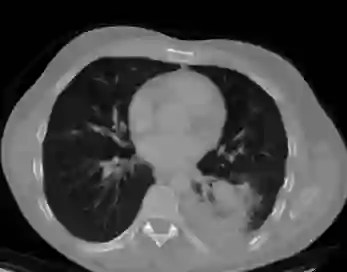

We propose a novel continual self-supervised learning (CSSL) framework for simultaneously learning diverse features from multi-window-obtained chest computed tomography (CT) images and ensuring data privacy. Achieving a robust and highly generalizable model in medical image diagnosis is challenging, mainly because of issues, such as the scarcity of large-scale, accurately annotated datasets and domain shifts inherent to dynamic healthcare environments. Specifically, in chest CT, these domain shifts often arise from differences in window settings, which are optimized for distinct clinical purposes. Previous CSSL frameworks often mitigated domain shift by reusing past data, a typically impractical approach owing to privacy constraints. Our approach addresses these challenges by effectively capturing the relationship between previously learned knowledge and new information across different training stages through continual pretraining on unlabeled images. Specifically, by incorporating a latent replay-based mechanism into CSSL, our method mitigates catastrophic forgetting due to domain shifts during continual pretraining while ensuring data privacy. Additionally, we introduce a feature distillation technique that integrates Wasserstein distance-based knowledge distillation (WKD) and batch-knowledge ensemble (BKE), enhancing the ability of the model to learn meaningful, domain-shift-robust representations. Finally, we validate our approach using chest CT images obtained across two different window settings, demonstrating superior performance compared with other approaches.

翻译:我们提出了一种新颖的持续自监督学习框架,用于同时从多窗位获取的胸部计算机断层扫描图像中学习多样化特征,并确保数据隐私。在医学影像诊断中构建鲁棒且高度可泛化的模型具有挑战性,主要源于大规模精确标注数据集的稀缺性以及动态医疗环境中固有的领域偏移问题。具体而言,在胸部CT中,这些领域偏移常由针对不同临床目的优化的窗位设置差异引起。以往的持续自监督学习框架通常通过复用历史数据来缓解领域偏移,但由于隐私限制,这种方法往往不切实际。我们的方法通过在未标注图像上进行持续预训练,有效捕捉不同训练阶段中已有知识与新信息之间的关联,从而应对这些挑战。具体而言,通过将基于潜在重放的机制融入持续自监督学习,我们的方法在确保数据隐私的同时,缓解了持续预训练中因领域偏移导致的灾难性遗忘。此外,我们引入了一种特征蒸馏技术,该技术整合了基于Wasserstein距离的知识蒸馏与批次知识集成,增强了模型学习具有意义且对领域偏移鲁棒的表征能力。最后,我们使用两种不同窗位设置获取的胸部CT图像验证了所提方法,结果表明其性能优于其他现有方法。